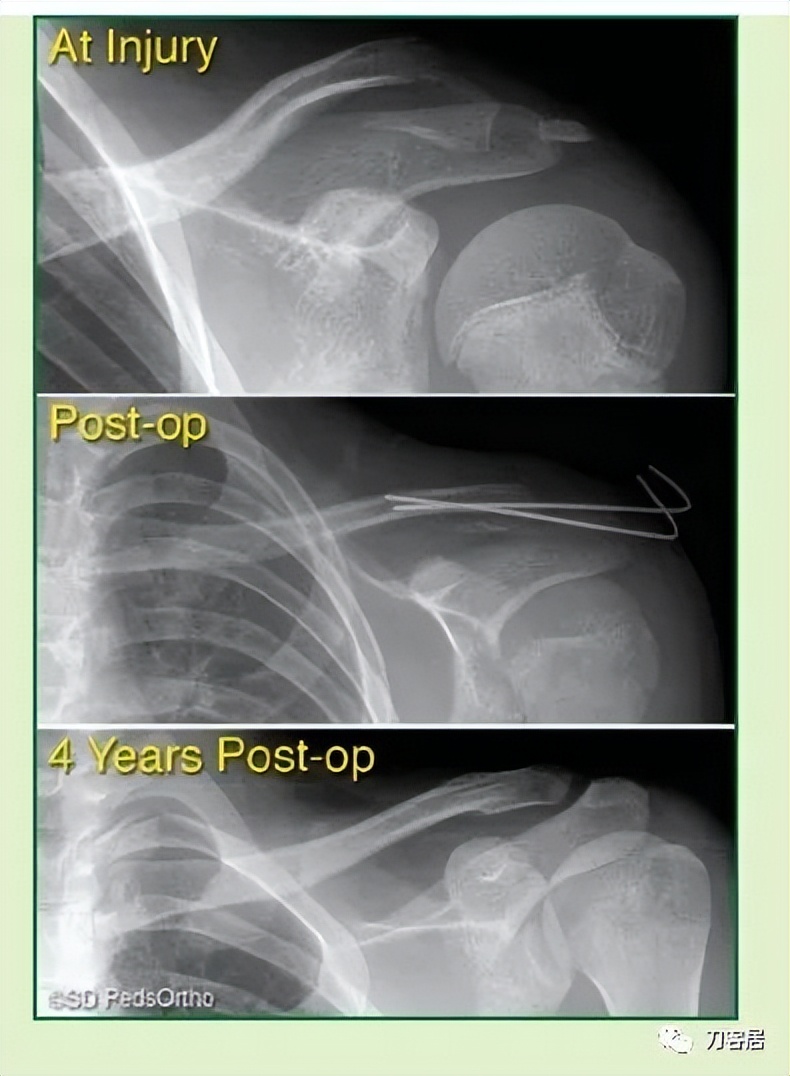

When surgical fixation is potentially required (Type IV, V, or VI injuries), controversy exists as to the optimal fixation technique with some favoring Kirschner wires, others hook plates, pre-contoured lateral clavicle plates, coracoclavicular fixation devices, or a combination thereof (Table 6-3). In the rare circumstance where pin fixation is used, we advocate significantly bending the pin outside the skin to minimize wire migration and weekly clinical evaluations until the pins have been removed (typically 3-4 weeks). The literature indicates that there can be significant complications from pin migration, including death. We believe each of these cases must be approached on an individual basis based on the size and comminution of the fracture fragments.

当需要手术固定时(IV、V或VI型骨折),采取何种固定技术存在争议,有人喜欢用克氏针,另有人喜欢钩板、预弯外侧锁骨板、喙锁固定装置或它们的组合(表 6-3)。在罕有的髓内针固定时,我们主张将针的一端折弯留置皮肤外侧,以防固定针移位,并且每周随访直至固定针去除(一般需要 3-4 周)。文献表明,固定针移位可能会导致严重的并发症,甚至死亡。我们认为,每个病例都应该根据骨折粉碎程度以及骨折块的大小,遵循个体化治疗原则,决定治疗方案。